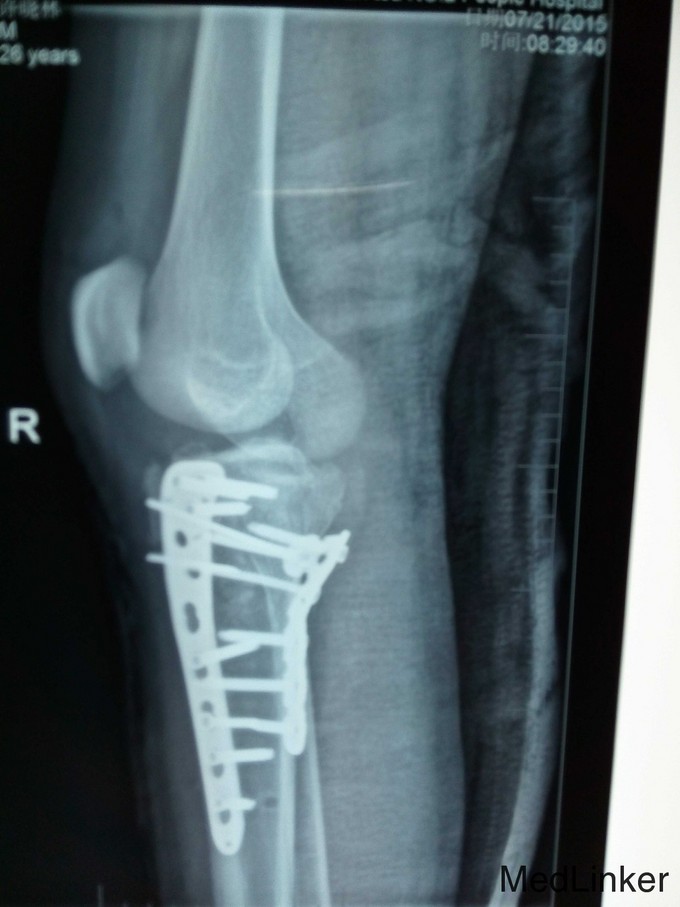

右胫骨平台粉碎性骨折(内外髁骨折) 入院后予跟骨骨牵引,一周后硬外麻下行胫骨平台骨折切开复位内固定术,术后伤口拆线痊愈出院。

胫骨平台骨折分6型,患者内外髁骨折,属第6型,手术采用内外侧切口钢板固定植骨术,该患者胫骨结节撕脱性骨折,故术中加用两条克氏针(螺丝无把持力)。请各位前辈赐教。